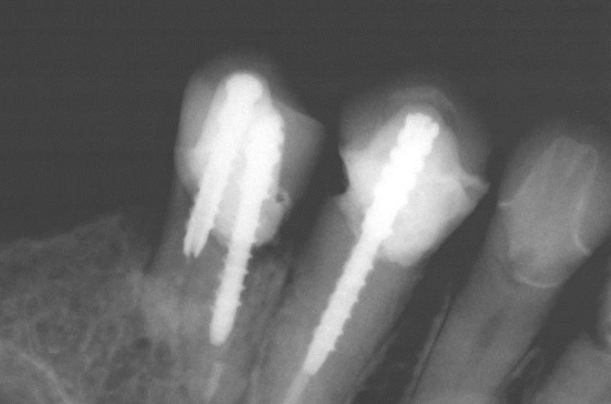

Root Canal Before and After in Mexico

Want to regain confidence in your smile? Our root canal gallery shows you real results: root canal pictures before and after that tell stories of transformation. Leave the pain and worry behind, and welcome a radiant, healthy smile. With our team of endodontic experts, each case is approached with care and precision, guaranteeing results that will take your breath away.

This is the most common root canal procedure, where the infected tooth pulp is removed and replaced with high-bonding resin and then the tooth is restored with crowns or fillings.

In the event that you have already had a root canal, and you are still in pain or your restoration has failed, a root canal retreatment will be performed to reseal and restore your tooth properly.